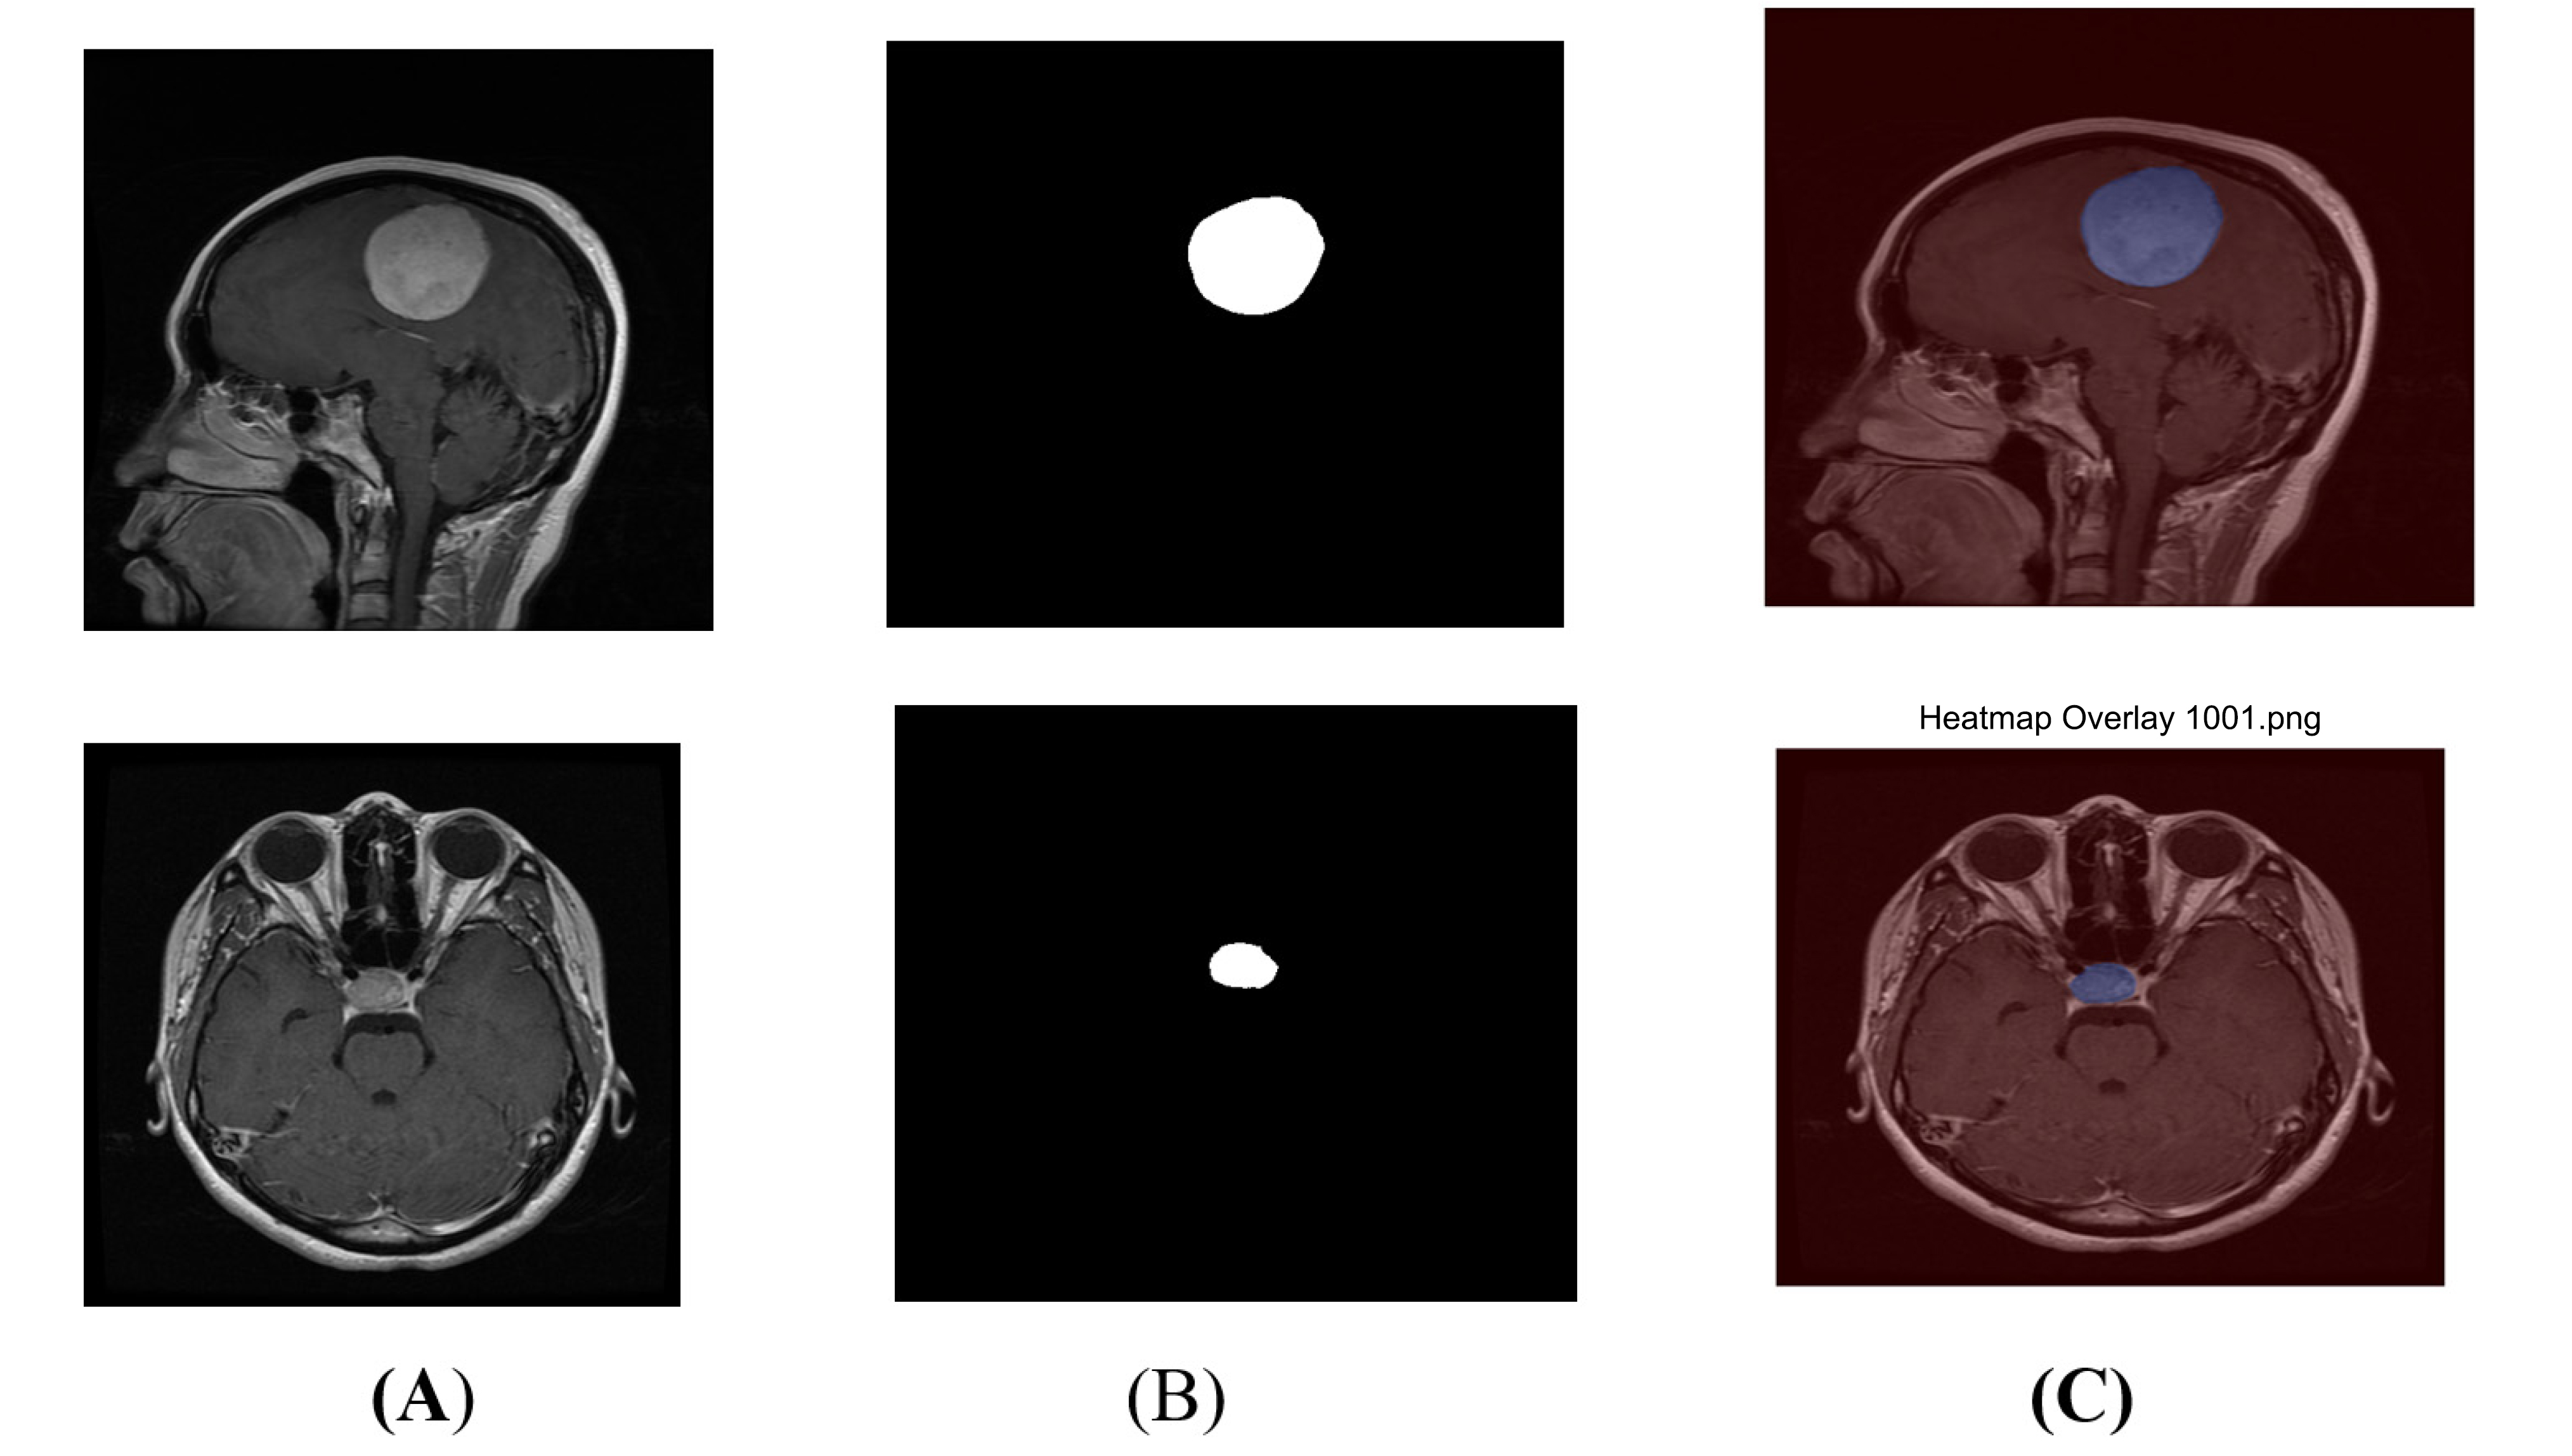

The segmented output mask is a plain black-and-white image and is separate from the original MRI scan, making it difficult to visualize the actual tumour area on the MRI. A heatmap overlay, which adds color to the tumour region, can be blended on top of the original MRI image, as shown in Fig. (11). This heatmap overlay helps non-technical AI users, such as doctors, quickly identify the predicted tumour region within the original MRI scans.

Heatmap overlay (A) original image (B) segmented output (C) heatmap overlay.